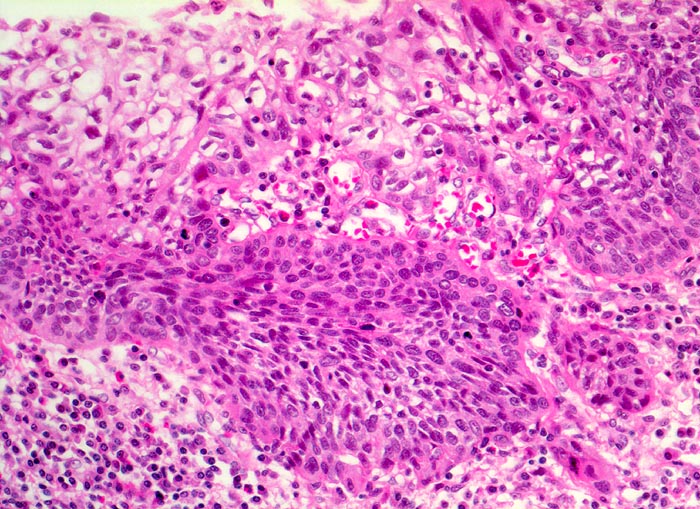

Mikroskopisch zeigen die meisten Plattenepithelkarzinome einen mittleren Differenzierungsgrad und eine wechselnd starke Verhornung. Das fortgeschrittene Karzinom infiltriert angrenzende Strukturen wie den Tracheobronchialbaum, die Aorta und den Nervus recurrens.